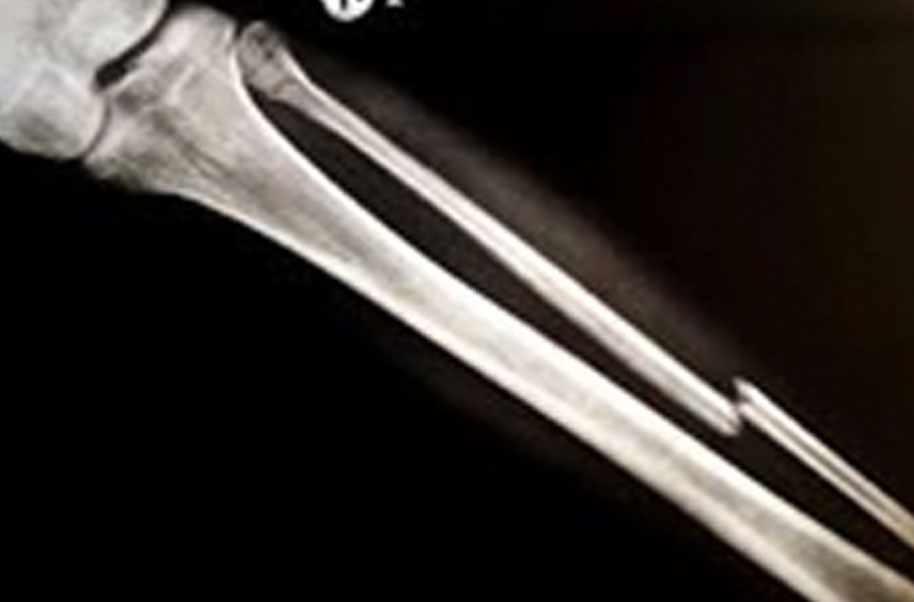

A complete or partial break in a bone.

- Treatment often involves resetting the bone in place and immobilising it in a cast or splint to give it time to heal. Sometimes, surgery with rods, plates and screws may be required.

Causes of bone fractures include trauma, overuse and diseases that weaken bones.